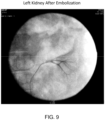

• PuraMatrix TM a peptide solution comprising Ac-RADARADARADARADA-NH 2 (Ac-Arg-Ala-Asp-Ala-Arg-Ala-Asp-Ala-Arg-Ala-Asp-Ala-Arg-Ala-Asp-Ala-NH 2 ) (SEQ ID NO: 58) in water was used as an embolic agent in a porcine model through angiography, gross necropsy assessment, and histopathology assessment.

• One female Yorkshire cross swine was tested. The weight of the swine at the time of testing was 46.5 kg. Feed and water were provided per standard operating procedures.

• a 2.5% test solution of the peptide solution was used. Approximately 800 microliters of the peptide solution was placed in an eppendorf tube. Approximately 200 microliters of Isovue-370 (Iopamidol) contrast agent was added. The liquids were mixed slowly so as to not create air bubbles.

• Table 2 Test Number Site Embolization Time Approximate Volume Placed Comments 1 Left Kidney Start 13:55 1.5 mL Successful embolization immediately following injection of peptide solution/Isovue Renal Artery 2 Right Kidney Start 14:12 1.5 mL Successful Renal Artery embolization immediately following injection. Slight flow reestablished at 14:18. Additional PuraMatrix TM / Iopamidol placed at 14:27. Angiogram showed full occlusion. 3 Hepatic Artery Start 14:58 2.0 mL Successful embolization immediately following injection. At 15:08, the artery remained occluded. At 15:32, the artery remained occluded. 4 Splenic Artery Start 15:17 3.0 mL Vessel was completed occluded at 15:21.